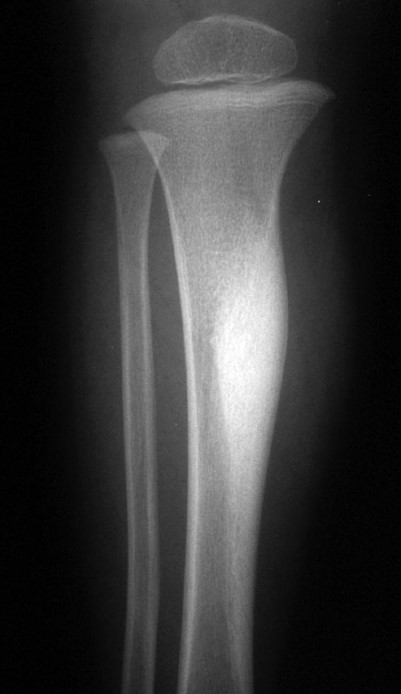

What is this?

Osteosarcoma